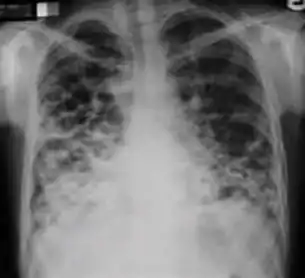

Chest X-ray of a person with advanced tuberculosis: Infection in both lungs is marked by white arrow-heads, and the formation of a cavity is marked by black arrows.